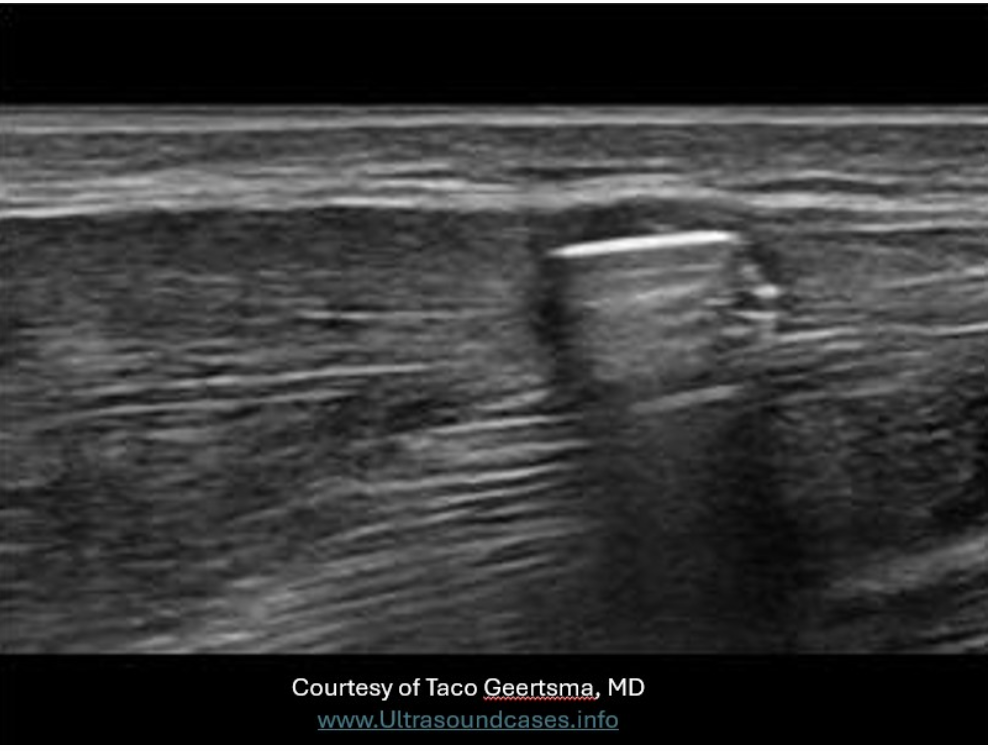

Which of the following statements is true regarding retroperitoneal lymph nodes?

C. Abnormal lymph nodes exhibit posterior enhancement.

Normal lymph nodes do not exhibit posterior enhancement. They are composed of mainly fatty tissue and lymphatic tissue which absorb and scatter sound. Abnormal lymph nodes do exhibit posterior enhancement due to the increased fluid within the inflamed tissues. The increased fluid within the tissues allows more sound to be transmitted through the node instead of reflected by the tissues. This leads to the enhancement of the reflection from the tissues posterior to the enlarged node. Lymph nodes larger than 1cm are considered suspicious and those over 2cm are considered abnormally enlarged.